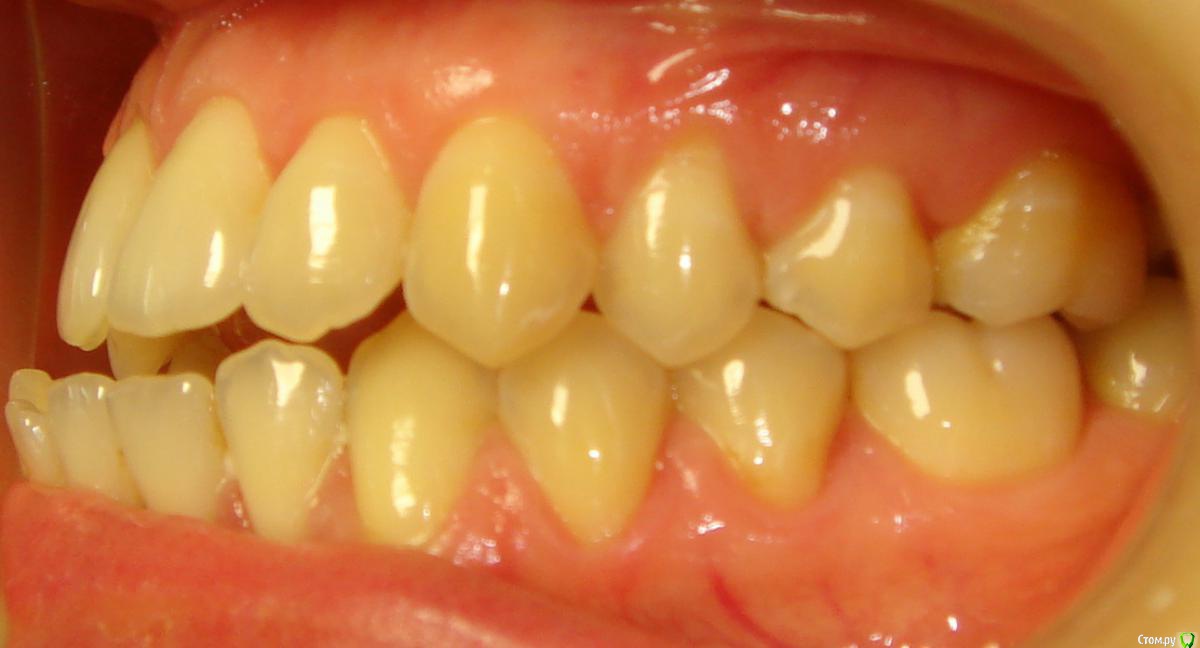

Opdihatop Опубликовано 4 марта, 2017 Поделиться Опубликовано 4 марта, 2017 И снова здравствуйте, коллеги. Вот такой вот случай к рассмотрению. Много лет назад пациентка уже проходила "камуфляжное" лечение. Со слов пациентки оно было закончено с передним открытым прикусом. Сейчас ситуация такая. Пациентка думает над ортохирургией, но меня смущает фронт н/ч. И по снимкам и по ситуации во рту корни 32, 31, 42, 43 зубов фенестрировали лингвальную кортикалку почти на всем протяжении, 33 - вестибулярную. Вопрос вот в чем: что делатьс этими зубами? Возможно ли их поставить на место? Или лучше не трогать, дольше простоят? Ссылка на комментарий

Opdihatop Опубликовано 29 мая, 2017 Автор Поделиться Опубликовано 29 мая, 2017 Как? Очень просто, "ДОЛЕЧИВАТЬ"! Тут фенестрация произошла из-за невылеченного инфантильного типа глотания и очень качественного (тут без сарказма) несъемного ретейнера. Исправь прошлый доктор язык, или поставь ретейнер хуже, так чтобы он его давление не выдержал и сломался, было бы все иначе. Ссылка на комментарий